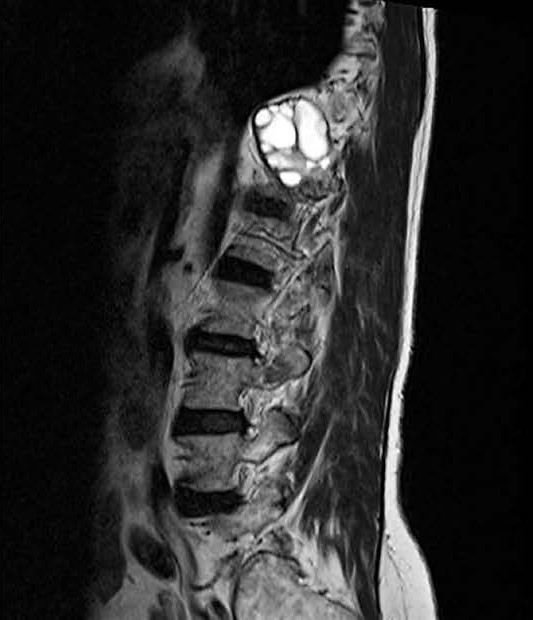

• Vertebral Hydatidosis: An Uncommon Cause of Low Back Pain

Catarina Melita, Paulo Ramos

113-114

DOI: https://doi.org/10.60591/crspmi.413